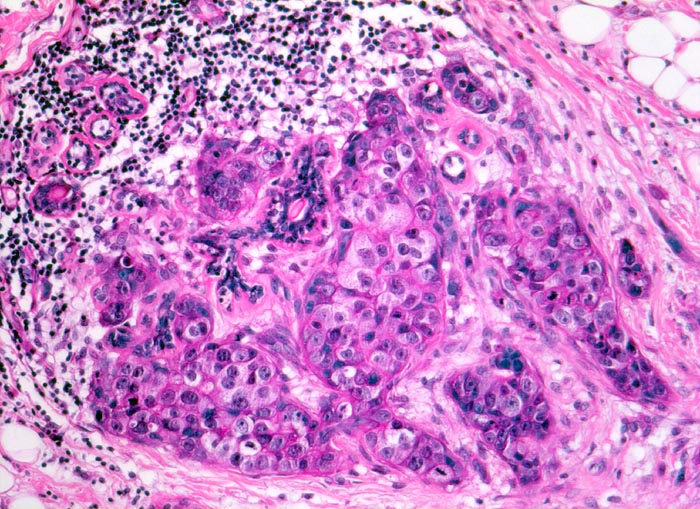

invasives duktales Mammakarzinom: Kanzerisierung eines Läppchens

Das Karzinom hat sich retrograd über den Ductus lactiferus in die Azini eines Läppchens ausgebreitet. Die läppchenförmige Anordnung der tumorbefallenen Azini ist noch erkennbar. Ein einzelner Azinus ist nicht tumorbefallen. Das Karzinom wächst an dieser Stelle nicht invasiv. Die tumorinfiltrierten Tubuli sind von einer Basalmembran umgeben.

Makroskopisch: derber weisser Herd von 2.2cm Durchmesser im oberen äusseren Quadranten.

Die Patientin hatte bei der Selbstuntersuchung einen harten Knoten in der rechten Mamma palpiert. Nach dem Nachweis von Karzinomzellen in der Feinnadelpunktion wurde eine Lumpektomie durchgeführt. Die intraoperative Schnellschnittuntersuchung ergab tumorfreie Resektionsränder.

160